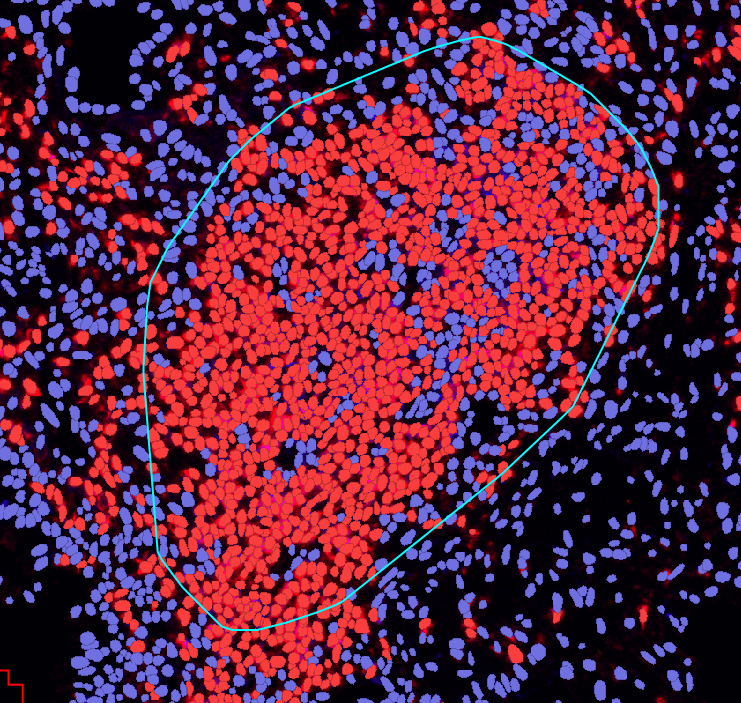

TLS分析功能,助力科研前沿三级淋巴结构的识别与分析

TLS自动识别,省去人工标记

荧光-TLS AI识别

HE-TLS AI识别